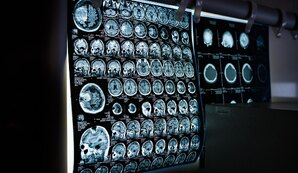

В Петербурге впервые провели операцию на мозг без трепанации

В городской больнице № 40 совершена первая в Петербурге операция с использованием фокусированного ультразвука под контролем МРТ.78.ru

Ультразвук воздействует только на поражённые участки мозга.78.ru